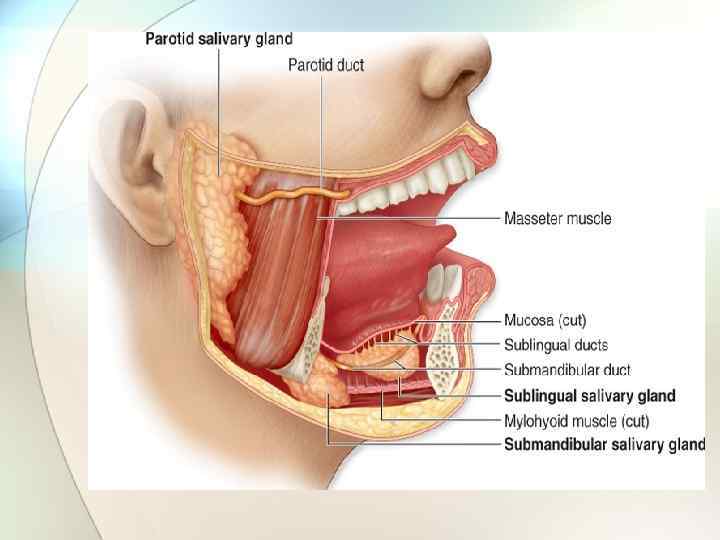

Слюнные железы. Слюна образуется сложными разветвленными альвеолярными или альвеолярно-трубчатыми слюнными железами: 3 пары крупных (работающие при стимуляции пищей циклически) и множество малых и мелких, располагающихся по всей поверхности слизистой рта - в области нижней поверхности языка (на кончике и корне), губ, щек (между мышечными пучками), твердого (немного) и мягкого (значительно больше) нёба. Мелкие и подъязычные железы функционируют постоянно, независимо от приема пищи, обеспечивая защитную, дыхательную, экскреторную, коммуникативную функции ЧЛО. NB! Все перечисленные железы являются аппаратами действия ФУС для формирования адекватного для проглатывания пищевого комка. Характер их секрета зависит от строения и типа концевых отделов – ацинусов и гландулоцитов.

Крупные слюнные железы. Ацинусы и секрет Околоушные – 2 типа клеток: 1 белковые – основные имеют базальный полюс (ядро, гранулярный ретикулум) и апикальный (секреторные гранулы с Поднижнечелюстные – 3 типа клеток: 1. белковые – основные до 80 % - имеют базальный полюс (много РНК) и апикальный полюс (серо-мукозный или серозный секрет) 2. смешанные белково-слизистые; белковым содержимым: αамилаза, ДНКаза); 3. миоэпителиальные клетки (и рыхлая соединительная ткань с малым 2 -миоэпителиальные клетки. количеством коллагена). Секрет белковый. Стенонов проток. Секрет смешанный. Вартонов проток. Подъязычные - 4 типа клеток: 1. белковые; 2. слизистые клетки; 3. смешанные – основные - серозные и слизистые клетки (содержащие нейтральные и кислые мукополисахариды); 4. наружные слизистые миоэпителиальные клетки. Секрет смешанный